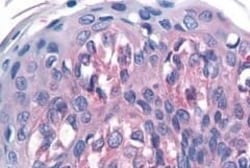

Invitrogen™ TAS1R1 Polyclonal Antibody

| Immunohistochemistry (Paraffin) | |

| Synthetic 16 amino acid peptide from 3rd cytoplasmic domain of human TAS1R1. | |

| Human, Canine, Bovine, Pig, Horse | |